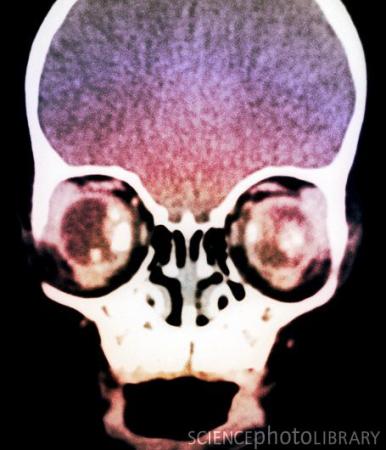

儿童视网膜母细胞瘤(CT扫描图)

在第一篇Nature文章中,研究人员揭示了儿童视网膜母细胞瘤(retinoblastoma)具有攻击性的机制。该研究发现解释了为什么该肿瘤发展迅速而其他类型的癌症形成则需要几年甚至几十年的时间。

众所周知,RB1抑癌基因丧失是导致胎儿发育期间视网膜母细胞瘤的重要原因,然而科学家们对这种癌症中正常细胞迅速转变成恶性肿瘤细胞的内在机制并不清楚。过去研究人员猜测有可能是RB1基因突变导致细胞基因组失稳,染色体断裂和重组。